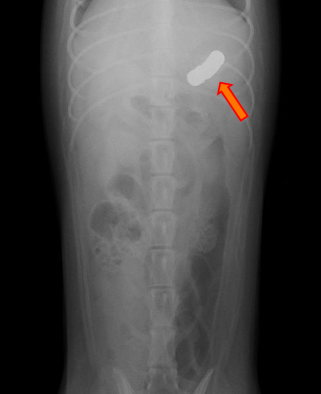

シェルティ(生後9か月、雌)

下痢を主訴に来院。この時に撮影したレントゲン画像が下の二枚です。

矢印で示したものは、金属類の異物だと思われます。

この異物が胃の中に留まっていました。

内視鏡を使って胃の中を観察してみると、やはり異物があったので、これを掴んで摘出しました。

このように、内視鏡はお腹を切らずに異物を摘出することができる優れた装置です。